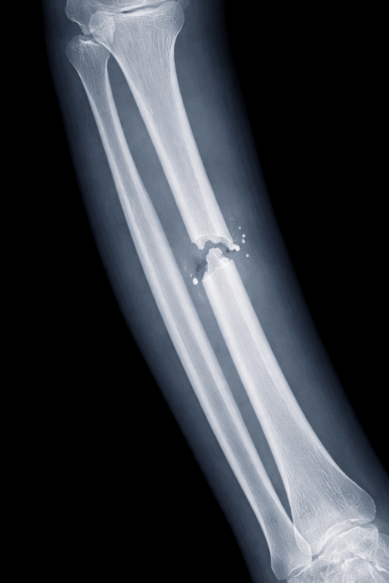

Diagnosis usually begins with the history of the injury and a physical examination. Mayo Clinic notes that the doctor will look for tenderness, swelling, deformity, and open wounds, then use imaging to confirm the fracture. X-rays are the main first test because they usually show the location and pattern of the break. CT or MRI may be needed when the fracture is complex, near a joint, or not clearly visible on plain X-ray.

Cleveland Clinic also notes that fracture diagnosis may involve X-rays, CT, MRI, or, in some cases, bone scans depending on the situation. NICE guidance further emphasizes structured assessment and management for non-complex fractures in emergency and orthopedic settings.